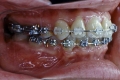

| 治療後2年経過時

| 治療前後の比較